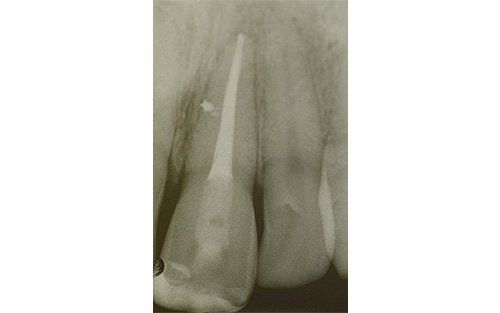

Frequenti, in età pediatrica, sono i traumi (sportivi e non). Come conseguenza i denti anteriori superiori (ovvero gli incisivi) sono i più esposti all’evento che può esitare in una frattura della corona con o senza il coinvolgimento della polpa, nella necrosi del dente (che può avvenire, più facilmente, senza alcuna frattura della corona dentale), oppure in quel panel di complicanze che vanno dalla lussazione ai traumi intrusivi o estrusivi, fino all’ avulsione, cioè la fuoriuscita completa del dente dall’alveolo.

I denti da latte traumatizzati più spesso vanno incontro a necrosi con conseguente cambiamento di colore, divenendo grigiastri, segno della morte delle cellule della polpa dentaria. In altre occasioni, il dente può fratturarsi in maniera più o meno ampia: se il frammento viene ritrovato, potrà essere re-incollato in maniera invisibile, oppure verrà ricostruito con i materiali compositi.